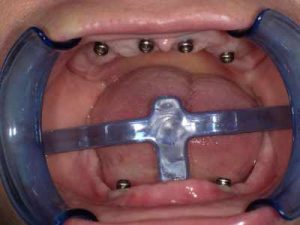

Jeśli nie jest możliwe wykonanie klasycznej odbudowy przy wykorzystaniu mostu protetycznego, który można oprzeć na stałych zębach pacjenta, stosujemy właśnie implanty, dzięki którym mocowanie protez ruchomych z bardzo dobrą stabilizacją jest możliwe. Już nawet dwa lub trzy implanty pozwalają na umocowanie protezy.